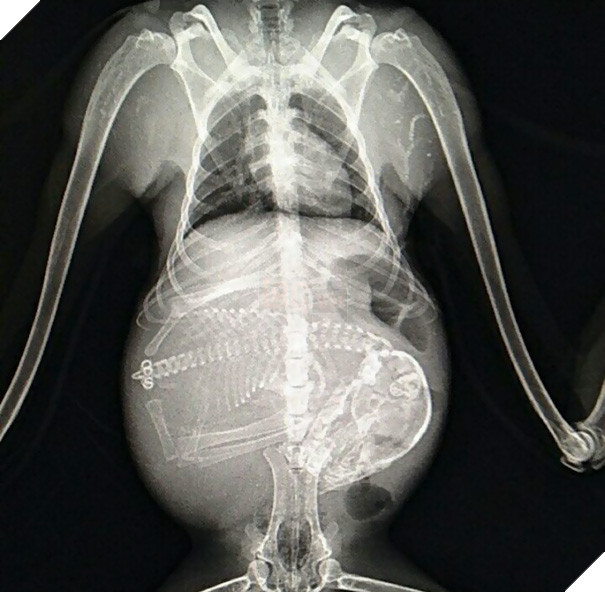

Một bà mẹ mèo đang mang thai. Thời gian thai kỳ của mèo khoảng 56 - 71 ngày, trung bình kéo dài khoảng 67 ngày và chúng có thể "sản xuất" 3 - 4 lứa mỗi năm.

Một hình ảnh khác về mèo mang thai. Có những loài vật mang thai 14 ngày là sinh nở, nhưng cũng có loài động vật cần 23 tháng để "mang nặng đẻ đau" khúc ruột của mình.